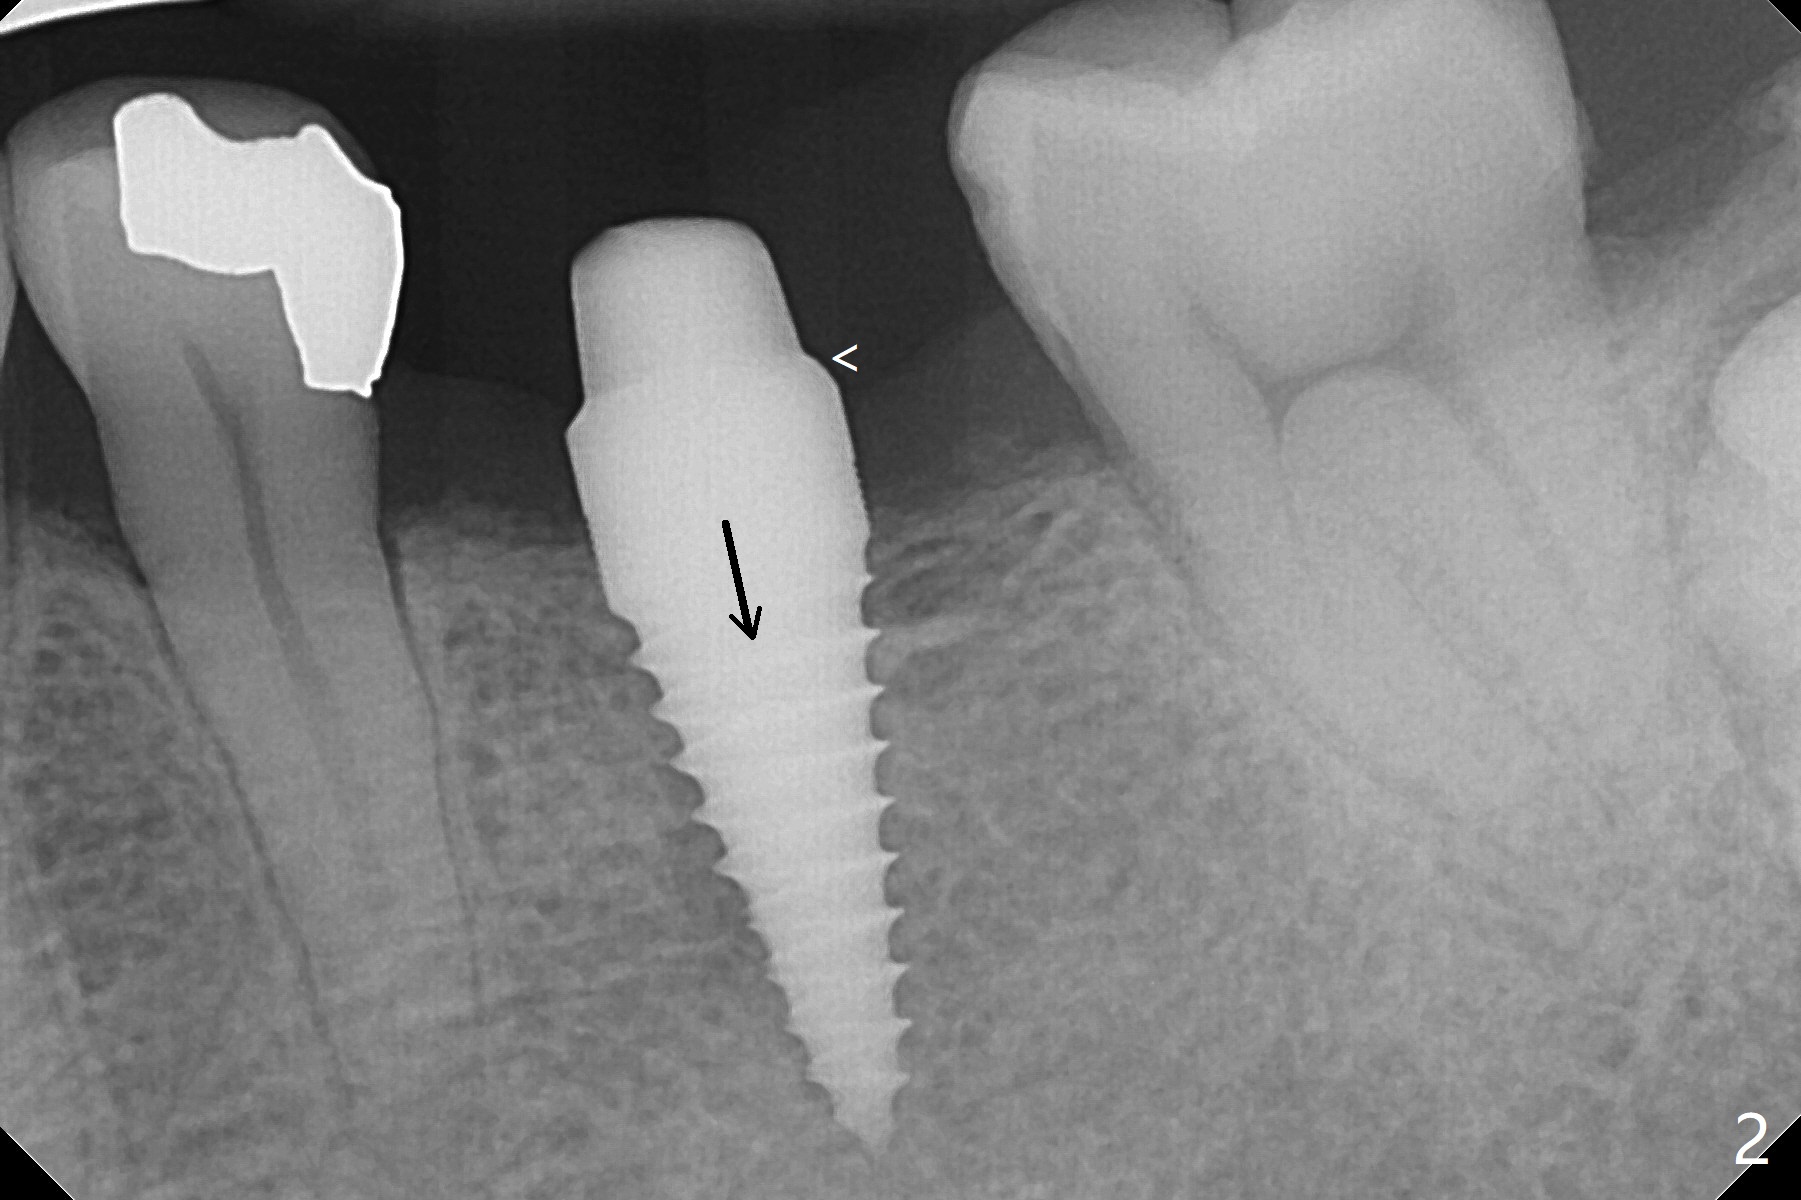

适当更改导板(为两段式接近圆柱状植体设计)钻洞顺序(根尖钻头小,而一段式植体根尖特别尖),5x14毫米一段式软组织水平植体植入,扭力大约35Ncm(图一),略微种深(图二:长箭头)后,磨短基台(与图一对比;左上6伸长),颊侧,远中,舌侧边缘降低(图二,三:<;增加基台高度,提高牙冠固位),制作临时牙冠(图四:P),主要目的将近中牙龈推向近中(图三:空箭头),暴露近中基台边缘,以后好取模。总之,一段式植体需要考虑临时修复。术后两个月临时牙冠和周围牙龈正常(图五)。术后4.5月轻度骨质吸收(图六),临床上看不出来螺纹将要暴露,取模。病人抱怨用临时牙冠咀嚼疼痛,不咬后没有不舒服,其实临时牙冠咬合面穿孔,牙龈正常,永久粘固剂没有外溢(图七)。术后4.5-6个月植体周围骨质吸收(图六,七)。牙槽嵴处钻洞应与植体直径一样才能减少骨质吸收。